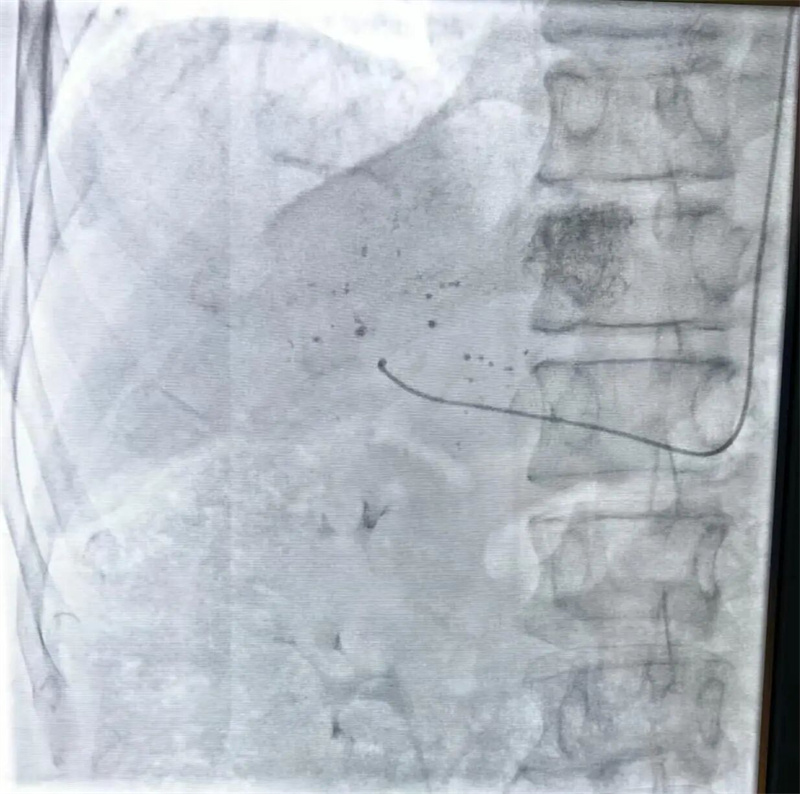

10月20日,放射线科主任尚祥武、主治医师陈志伟通力协作,手术顺利实施。

仅4分钟,穿刺成功!

导管经左侧远桡动脉进入肝脏,注入栓塞剂和化疗药物,精准作用于病灶。40分钟后,手术圆满完成。